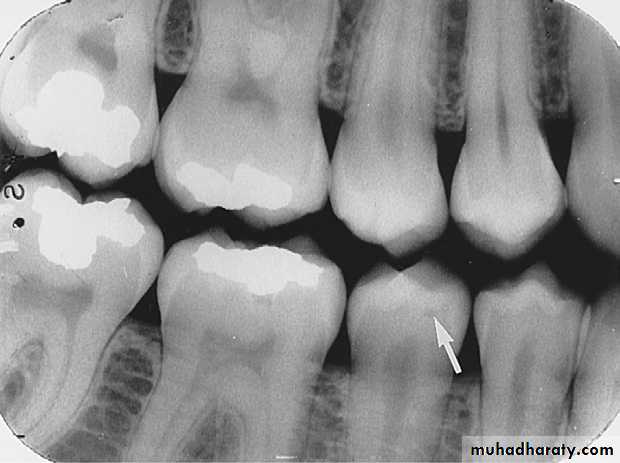

An incipient carious lesion on the distal surface of the mandibular second premolar.

An advanced carious lesion, which extends through the dentino-enamel junction (DEJ) and into dentin, seen on the distal surface of the mandibular first molar.

Advanced Interproximal Caries

Advanced lesion identified by arrows.